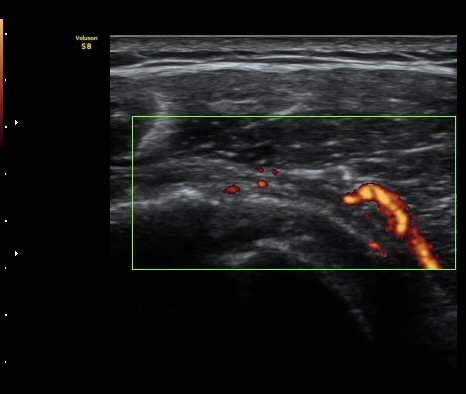

±Ø»ó°Ç ¸»´ÜºÎ Á¾´Ü¸é°Ë»ç¿¡¼­ ±Ø»ó°Ç°ú Á¡¾×³¶³» ¼®È¸È­°¡ °üÂûµÈ´Ù(±×¸² 4, 5).

ÆÄ¿öµµÇ÷¯°Ë»ç¿¡¼­ ±Ø»ó°Ç°ú Á¡¾×³¶ÁÖÀ§¿¡¼­ ¼ö¾×Àú·ù°¡ °üÂûµÈ´Ù(±×¸² 6, 7).